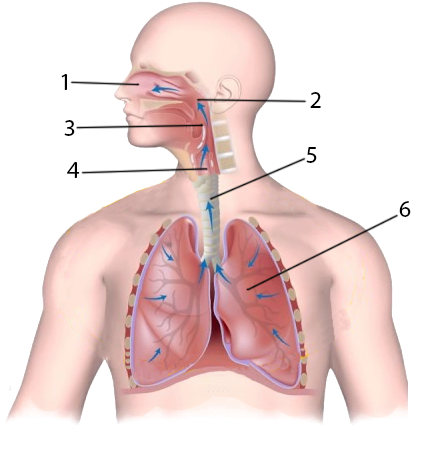

Схемы дыхания: Пневмоторакс на изображениях